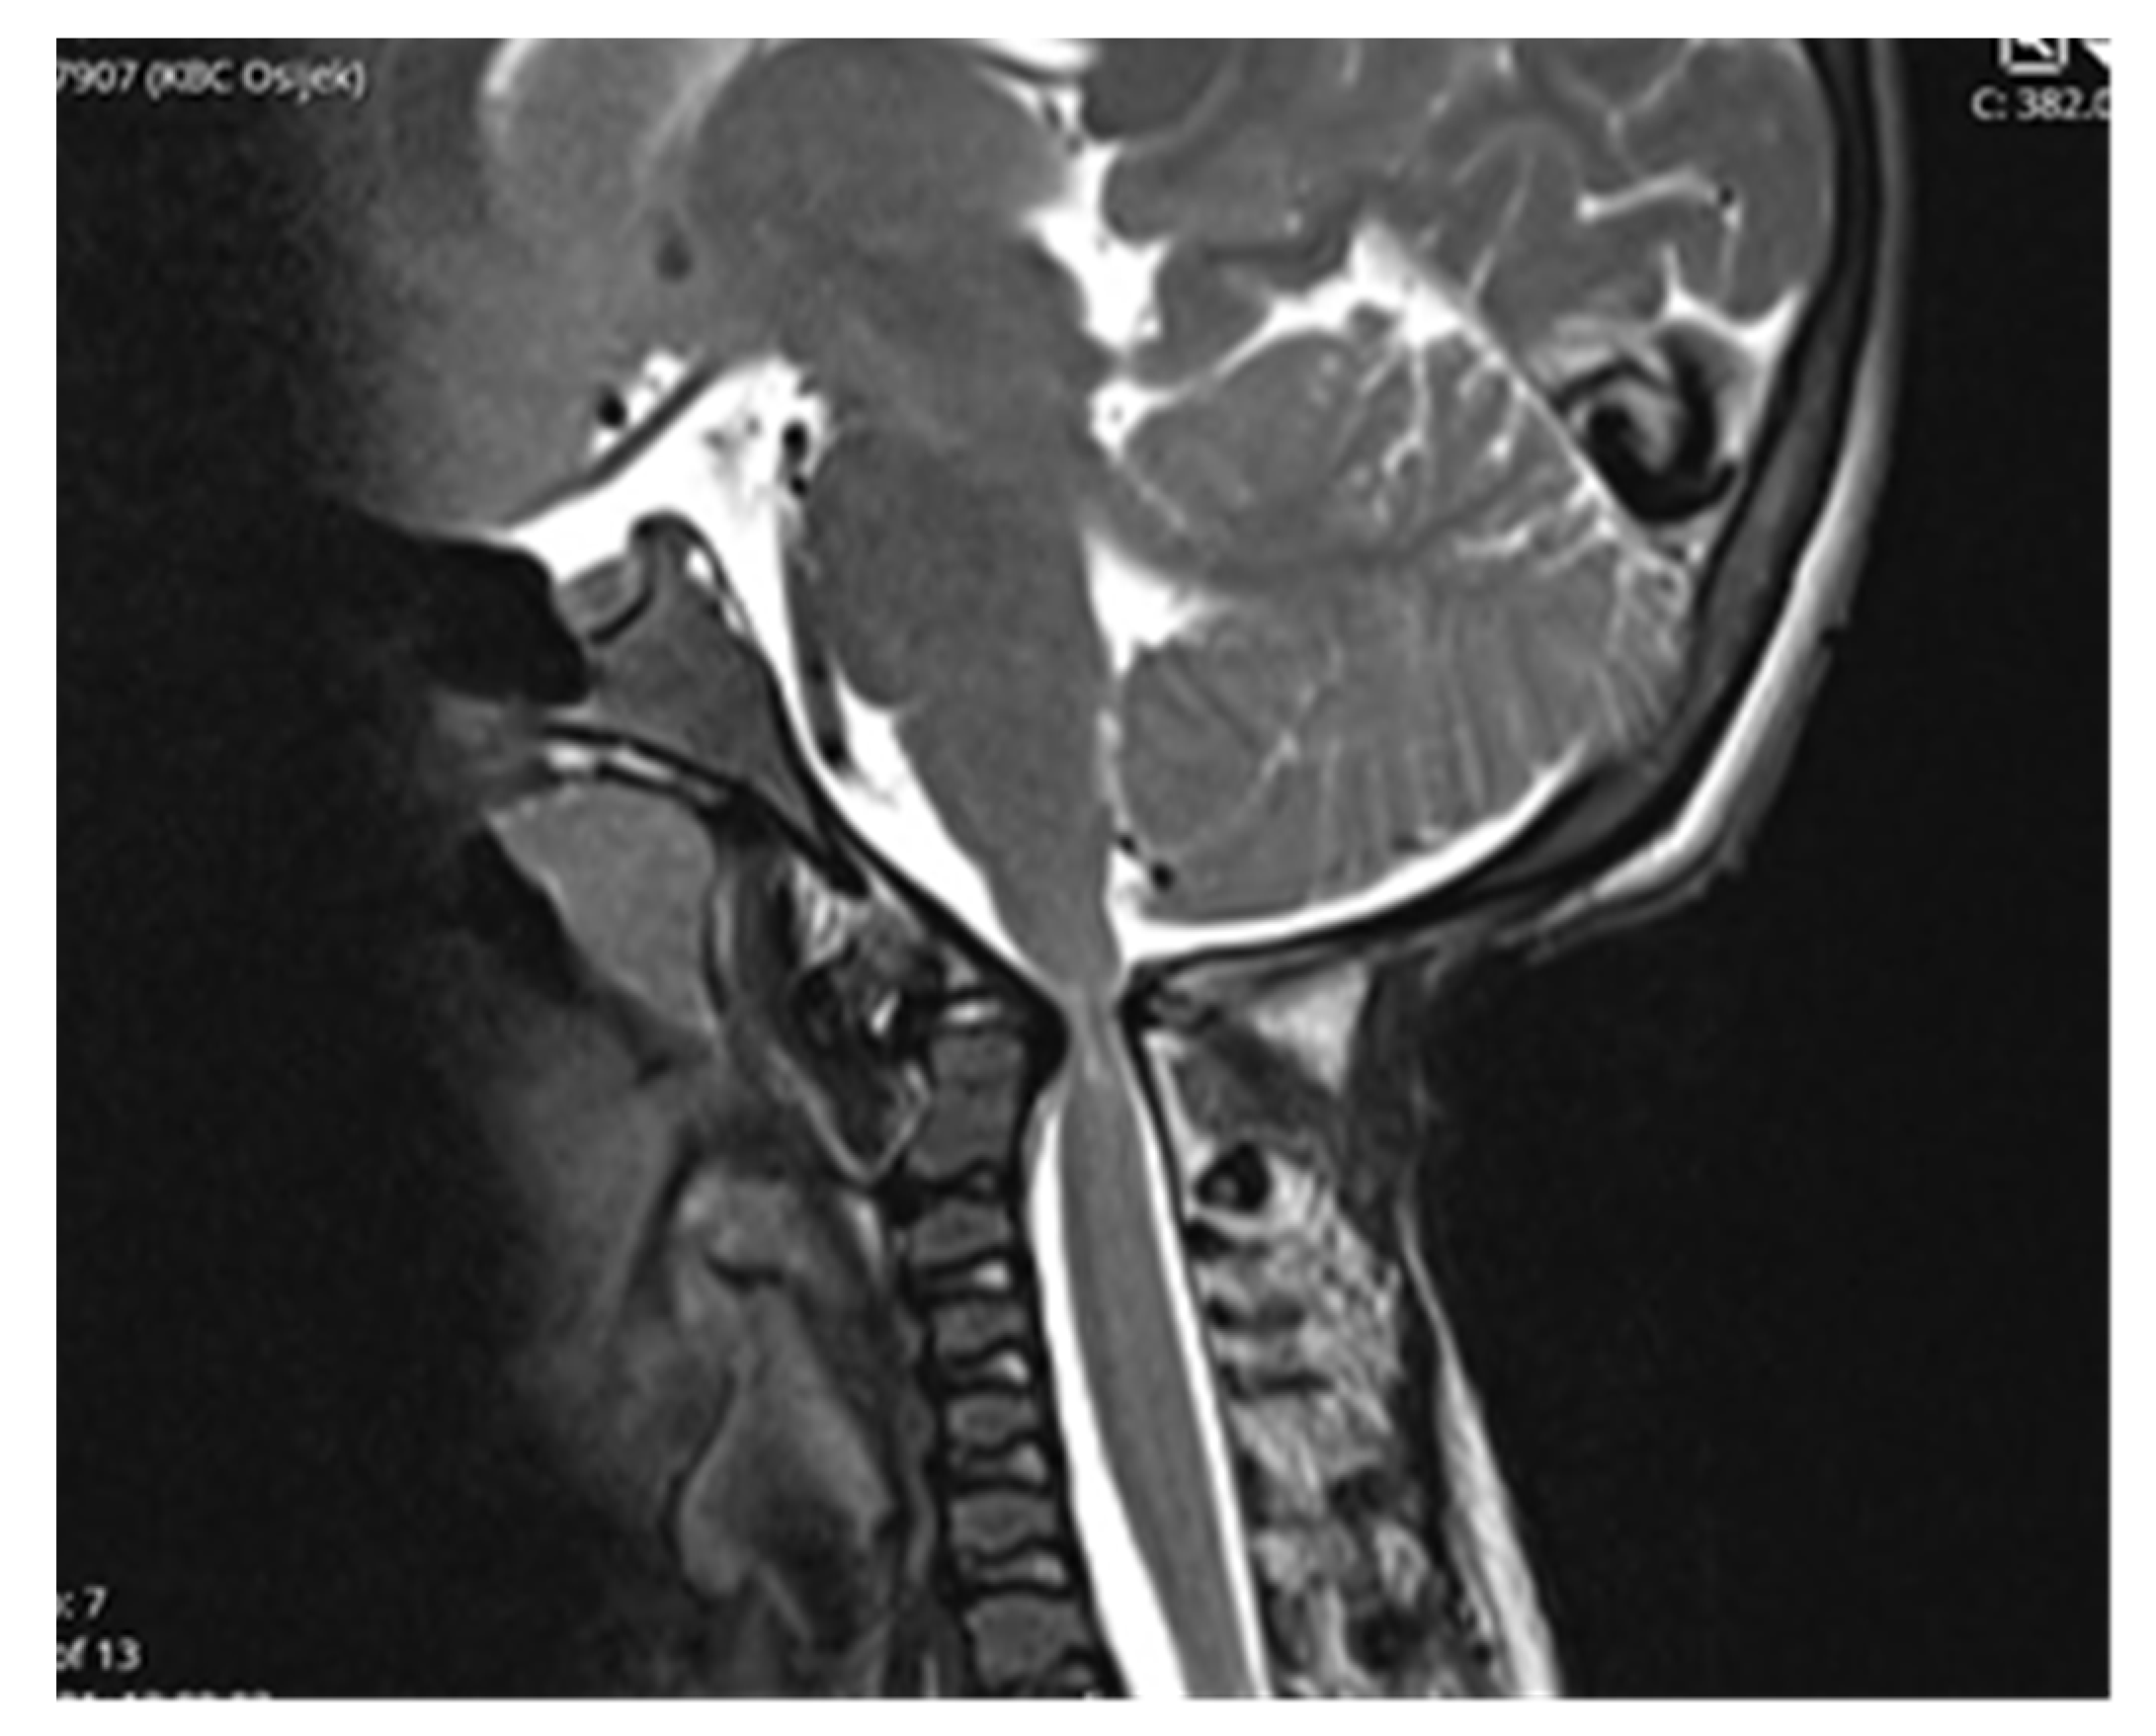

Follow-up MRI scan of cranio-cervical junction after three months and one year revealed residual stenosis of CCJ and myelopathy of cervical medulla. Nevertheless, the postoperative diameter of decompressed CCJ was insignificantly wider in the sagittal and axial planes compared to preoperative MRI scan (Figure 5).

Despite an adequate decompression of the CCJ, a postoperative follow-up MRI scan revealed only a limited widening of the diameter of the cranio-cervical junction caused by radiologically confirmed atlanto-axial instability. There was no sign of regression of myelopathy. The authors did not confirm the utmost benefit of surgery according to radiological follow-up.

Figure 5. Postoperative MRI revealed insignificant radiological differences comparing to preoperative scanning with persistent myelopathy (15 years of age).